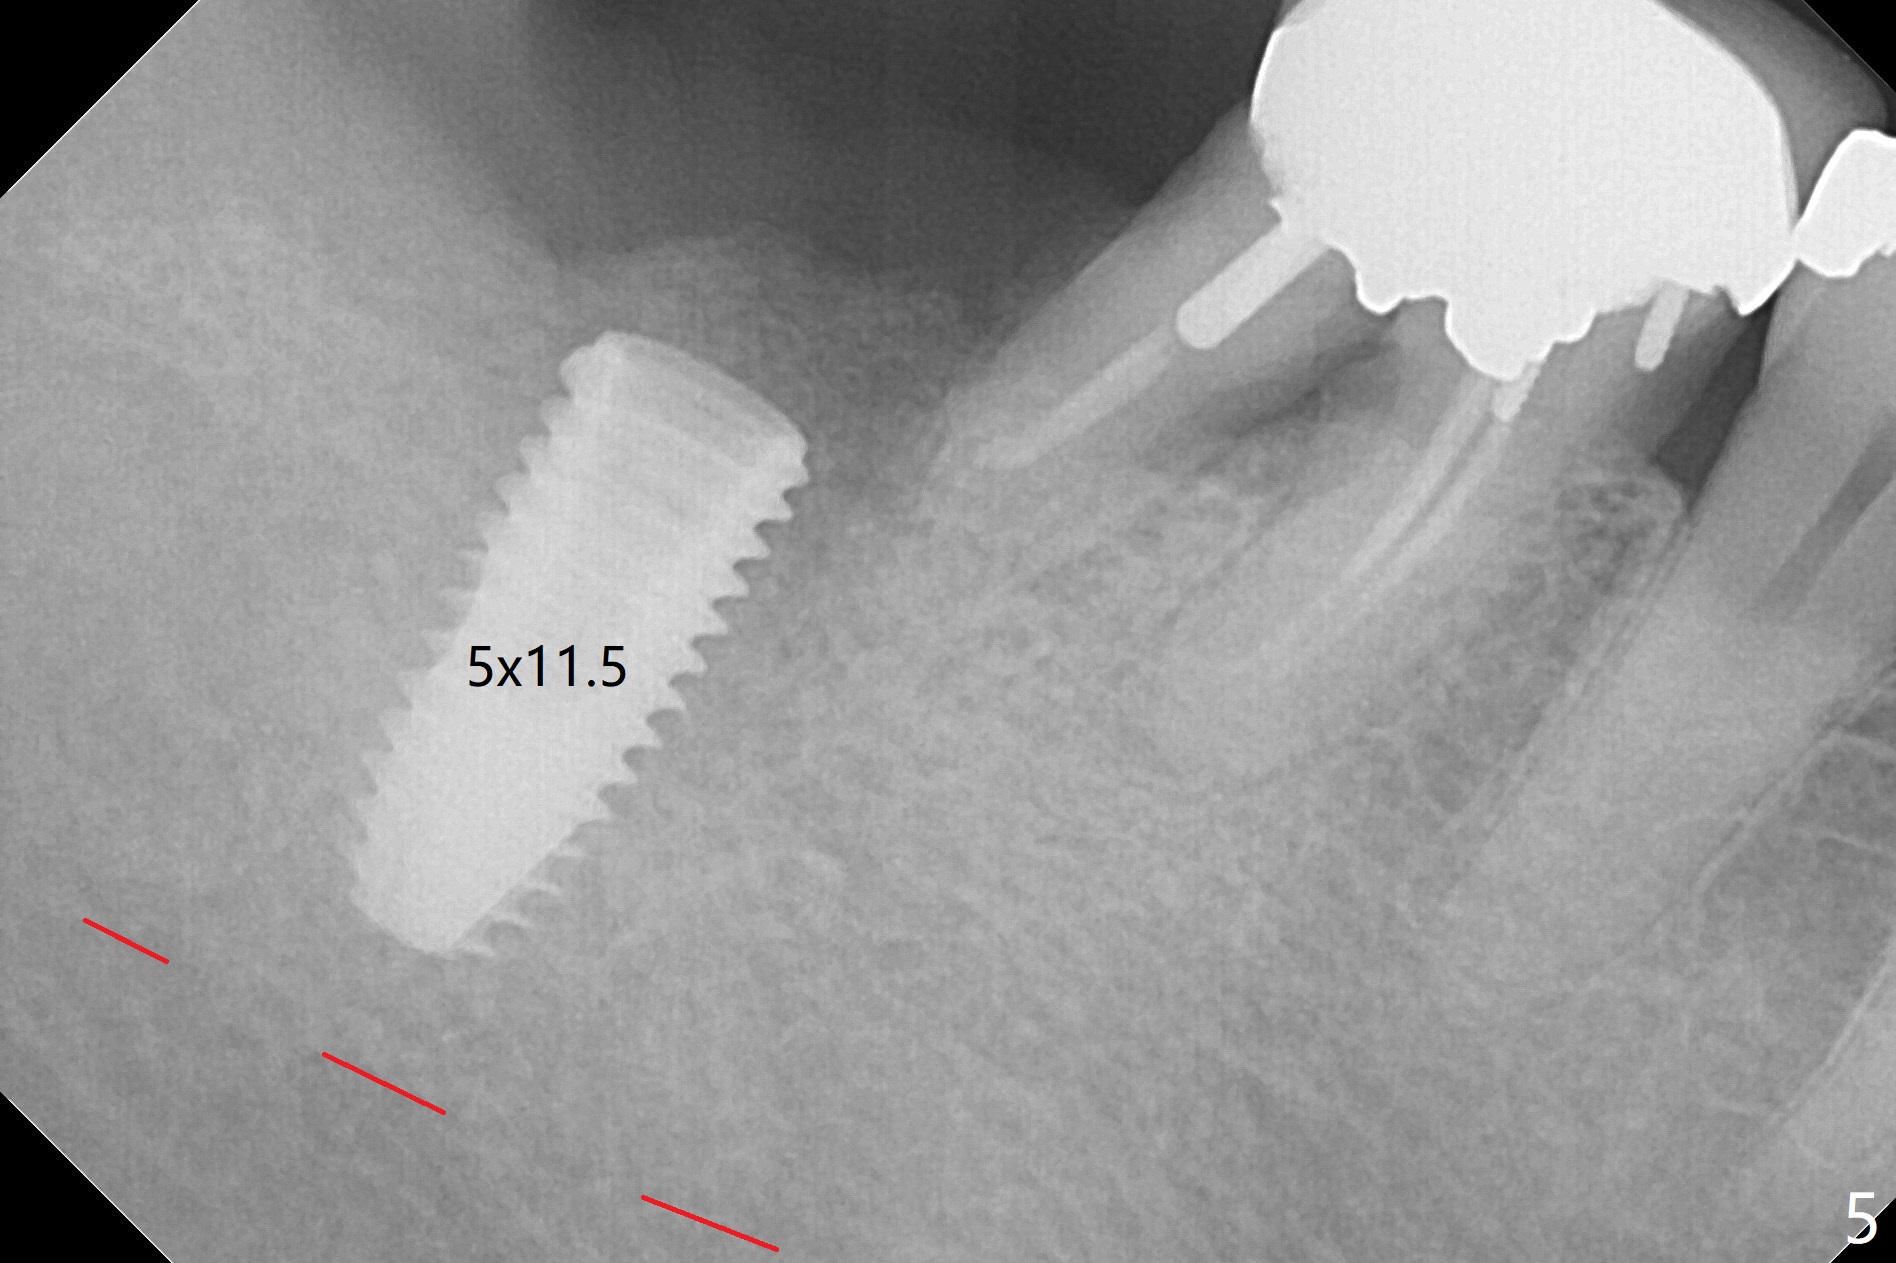

After extraction of the 2nd molar with buccal fistula (Fig.1), osteotomy is initiated beyond the socket for 4 mm (Fig.2,3). Following moving the osteotomy distal and sequential osteotomy, a 4.5x11.5 mm dummy implant is placed equicrestal buccally (Fig.4 ^) with stability; the dummy abutment is 6.5x5(4) mm. A 5x11.5 mm (definitive) implant achieves .>20 Ncm insertion torque (Fig.5). With placement of a 6.5x4(5) mm abutment, Vanilla (Fig.6 *) and Osteogen plug over the graft and in the socket of #32, periodontal dressing is applied. The implant at the 2nd molar placed much deeper than the 1st molar seems to be risky in term of the Inferior Alveolar Canal (Fig.3-6 red dashed line). Several carpules of anesthetics have to be administered in an infiltration manner for pain control. Fortunately there is no postop paresthesia. For an un-compliant patient, socket preservation is a better option. The implant seems to have osteointegrated 4 months postop (Fig.7).